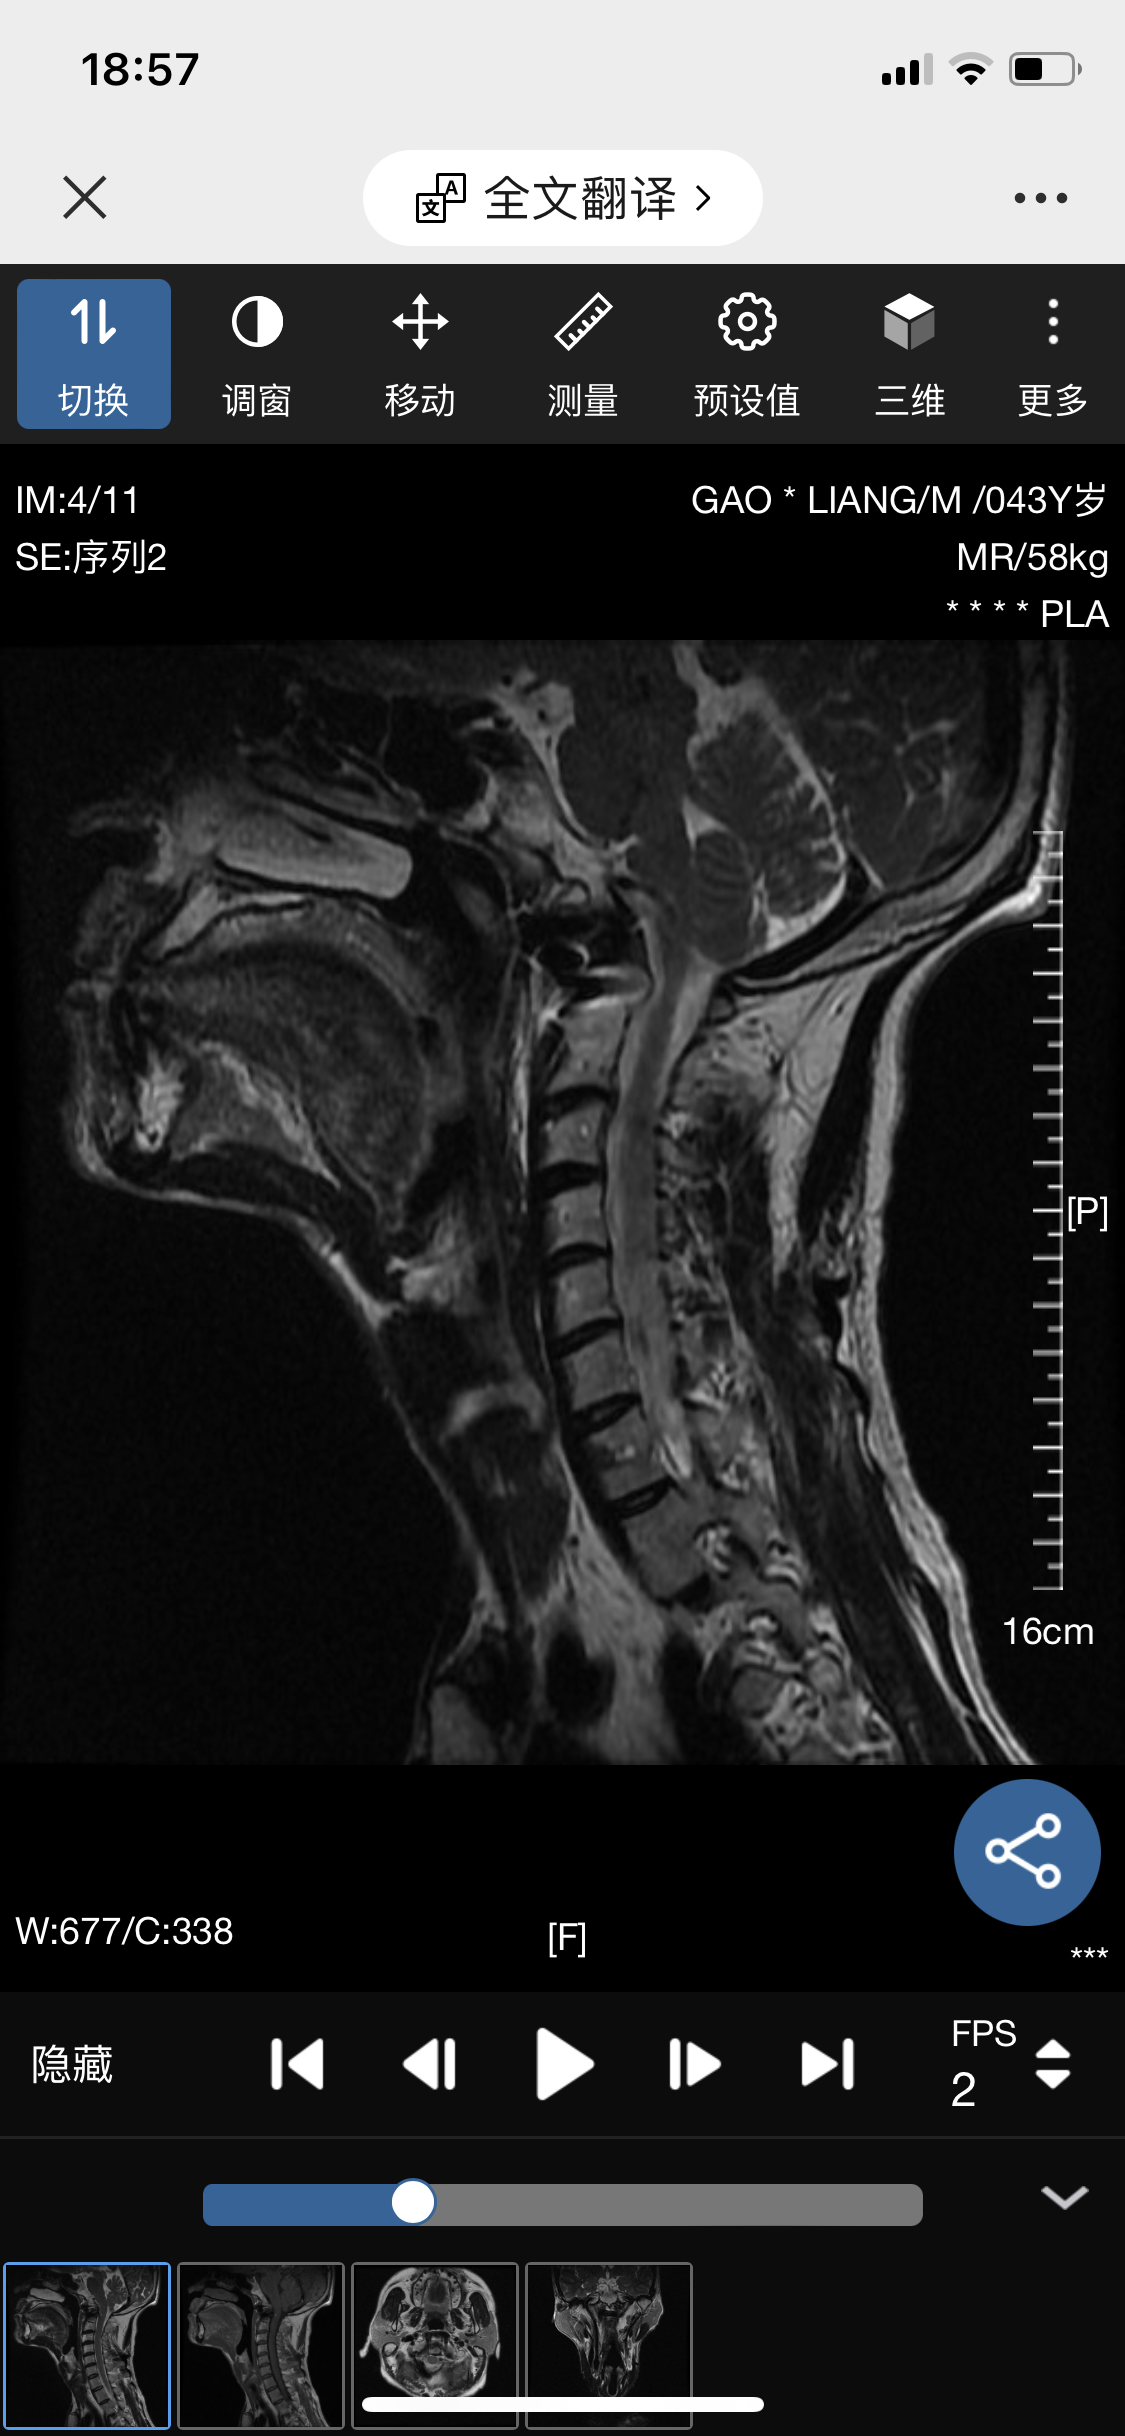

• 诊断:寰枢椎脱位

• 影像: